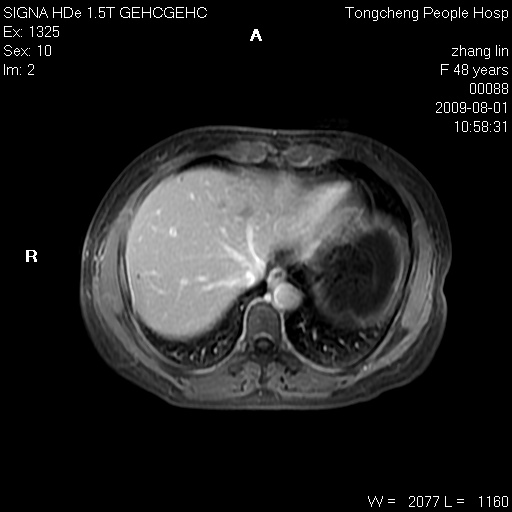

女,48岁。健康体检,彩超发现右肾占位性病变。平素健康。

临床诊断:右肾占位性病变,性质待定(囊肿?肿瘤?)。

上中腹部mr平扫+增强扫描,图像如下:

右肾上极见一类圆形病灶,t1wi呈等信号t2wi呈等高混杂信号,三期增强无强化,边界清---考虑囊肿出血。

同反相位均表现为等信号,病变无强化,考虑含蛋白的囊肿可能,弥散加权相或许有些帮助,